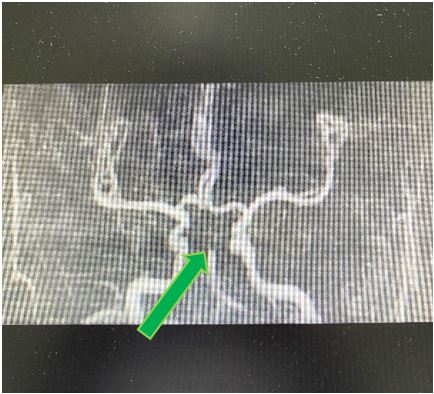

王虎清教授立即查看患者,与患者家属充分沟通取得同意后,神经内科介入团队其他成员范清雨主治医师、张宏医师、蒋鹏鹏护士迅速到位,导管室迅速启动,在麻醉科代志明医师的协助下为该患者进行了脑血管造影,造影证实患者基底动脉远端闭塞,同时合并右侧椎动脉闭塞,左侧椎动脉开口及V4段线样狭窄、颅内段显影不佳。神经内科介入团队医师经严谨讨论后,考虑患者目前病情危重,给予基底动脉尖负压抽吸取栓,一把完全再通,患者基底动脉血流恢复,双侧大脑后动脉及小脑上动脉显影良好。考虑患者右侧椎动脉闭塞,左侧椎动脉开口及V4段线样狭窄,仍有发生栓塞及椎基底动脉闭塞的风险,遂继续行椎动脉开口及V4段球囊扩张+支架成形术,术程顺利,手术结束时已是10月29日的凌晨。

患者术前及术后的脑血管造影DSA对比图

术中从基底动脉尖取出的血栓